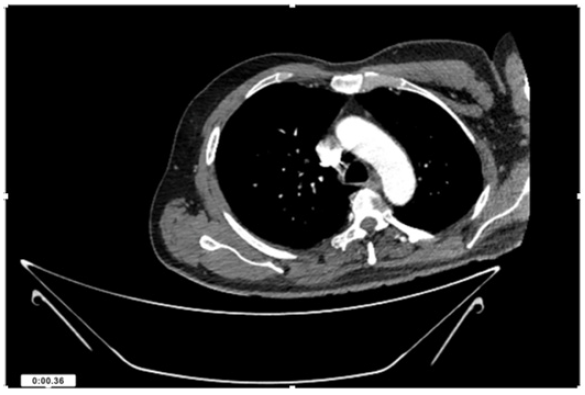

55-years-old chronic smoker had acute, severe pain in the right upper limb for one week; it was cold upto mid arm with skin discoloration. He also noticed numbness and weakness of movement of elbow joint. He underwent below elbow amputation in February 2023 for acute ischemia of left upper limb. He was a current chronic smoker; 15 pack year. General condition was weak; temperature was normal; blood pressure was 100/60mmHg; heart rate was 92/minutes with sinus rhythm; SpO2 was 97% on air; heart was normal. In lower extremities, all peripheral pulses were intact. Local Examination of right upper limb revealed as follows: tenderness; coldness; discoloration; decreased motor function and sensory modalities. Axillary, brachial and radial pulses were not palpable. Hand-held Doppler failed to detect any signal in arterial system; therefore, we arranged for emergency embolectomy. complete occlusion of right upper limb arterial system Full blood count showed high hemoglobin (14.6gm%); normal total WBC and platelet count. Coagulation profile was normal. Parenteral unfractionated heparin, antibiotics, tramadol, proton-pump inhibitors, anti-platelets and HMG CoA reductase inhibitors were given. Doppler ultrasound demonstrated complete occlusion of right upper limb arterial system. CT Angiogram illustrated occlusion of subclavian artery downwards on both sides. Figures 1-14 shows complete occlusion of right subclavian artery without collaterals. On Day ‘2’ of admission, the patient passed black tarry stool for 3 times. However, the vital signs were stable; blood pressure was 100/60mmHg; heart rate was 92/min; SpO2 was 97% on air; the abdomen was soft and not tender. Above elbow amputation was done on Day ‘2’ of admission. Intra-operative findings were as follows: (1) no active bleeding at brachial artery; (2) thrombosis along brachial artery; (3) muscle color and consistency were not healthy.

Figure 4: CT Angiogram at neck showing normal brachio-cephalic trunk, common carotid artery, and narrow right subclavian artery.

Figure 5: CT Angiogram at neck showing normal brachio-cephalic trunk, common carotid artery, and narrow right subclavian artery.

Figure 6: CT Angiogram at neck showing brachio-cephalic trunk, common carotid artery and narrow right subclavian artery.

Figure 7: CT Angiogram at neck showing brachio-cephalic trunk, common carotid artery and narrow right subclavian artery.

Figure 10: CT Angiogram at upper arm showing totally occluded right axillary artery; normal internal carotid artery and external carotid artery.